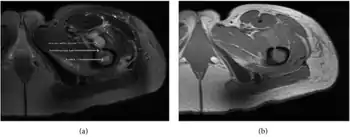

| a,b) MRI showing the Brodie's abscess in the left proximal femur | |

Sagittal T1-weighted fat-suppressed post gadolinium image showing the extent of the multiloculated intramedullary abscess.